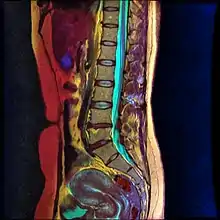

There are multiple posterior percutaneous approaches, but no clinical evidence suggests that any one technique is more efficient than the rest. The posterior approaches generally utilize two needles, one at each side of the L1 vertebral body pointing towards the T12 vertebral body.[3]

Lumbar sympathetic neurolysis is performed between the L1-L4 vertebrae with separate injections at each vertebra junction. The chemicals used for neurolysis of the nerves cause destructive fibrosis and cause a disruption of the sympathetic ganglia. The vasomotor tone is decreased in the area affected by the neurolysis, which in addition to arteriovenous shunting, create a light pink appearance within the affected area. Lumbar sympathetic neurolysis alters the ischemic rest pain transmission by changing norepinephrine and catecholamine levels or by disturbing afferent fibers. This procedure is mainly used only when other feasible approaches to pain management are unable to be used.[6]

Lumbar sympathetic neurolysis is performed by using absolute alcohol, but other chemicals such as phenol, or other techniques such as radiofrequency or laser ablation have been studied. To aid in the procedure, fluoroscopy or CT guidance is used. Fluoroscopic guidance is the most frequent, giving better real-time monitoring of the needle. The general technique of administering lumbar sympathetic neurolysis involves using three separate needles rather than one because it allows for better longitudinal spread of the chemicals.[6]